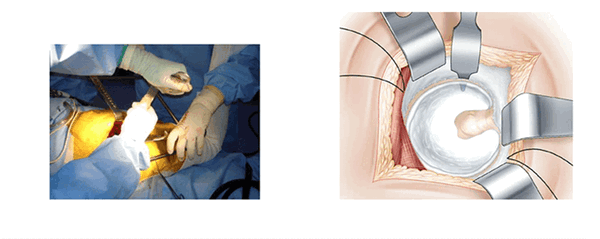

Голеностопный сустав помещается на опоре. Колено согнуто и повернуто вовнутрь. Поверхность кожи обрабатывают антисептиком и делают разрез. В разрезе видна большая ягодичная мышца. Таким образом открывают операционное поле. Большая ягодичная мышца рассекается атравматическим способом снизу вверх по направлению волокон. В нижней части разреза рассечение широкой фасции облегчает манипуляции. В рану вводится рамка Шарнли. Она будет держать края большой ягодичной мышцы в течении всей операции. Передний клапан рамки располагается по направлению большого вертела.

Экспозиция вертлужной впадины. (L’exposition du cotyle)

Три ретрактора располагаются вкруговую и открывают доступ к вертлужной впадине. Каждый раз меняется положение ноги, что облегчает расположение каждого ретрактора. Изогнутый ретрактор устанавливается вслепую, ощупью. Его конец проталкивают вглубь вертлужной впадины, чтобы захватить край переднего рога после перфорации капсулы на уровне кости.